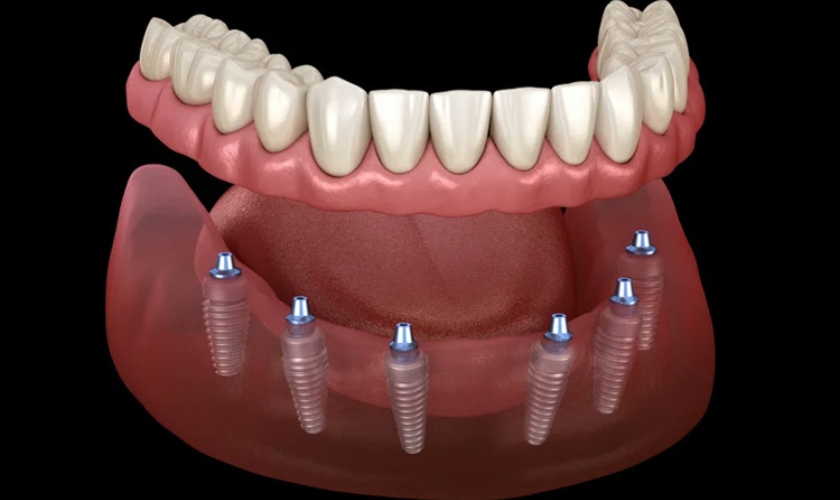

Full mouth teeth implants, also known as full-arch implants, involve the replacement of all teeth in either the upper or lower jaw, or both, with a series of implants that support a full arch of prosthetic teeth. Unlike traditional dentures, these implants are permanently fixed, providing a stable and natural-looking solution.

Full mouth dental implants are ideal for individuals who have lost most or all of their teeth due to decay, disease, or trauma. Candidates should have sufficient bone density in the jaw to support the implants or be willing to undergo bone grafting if necessary.